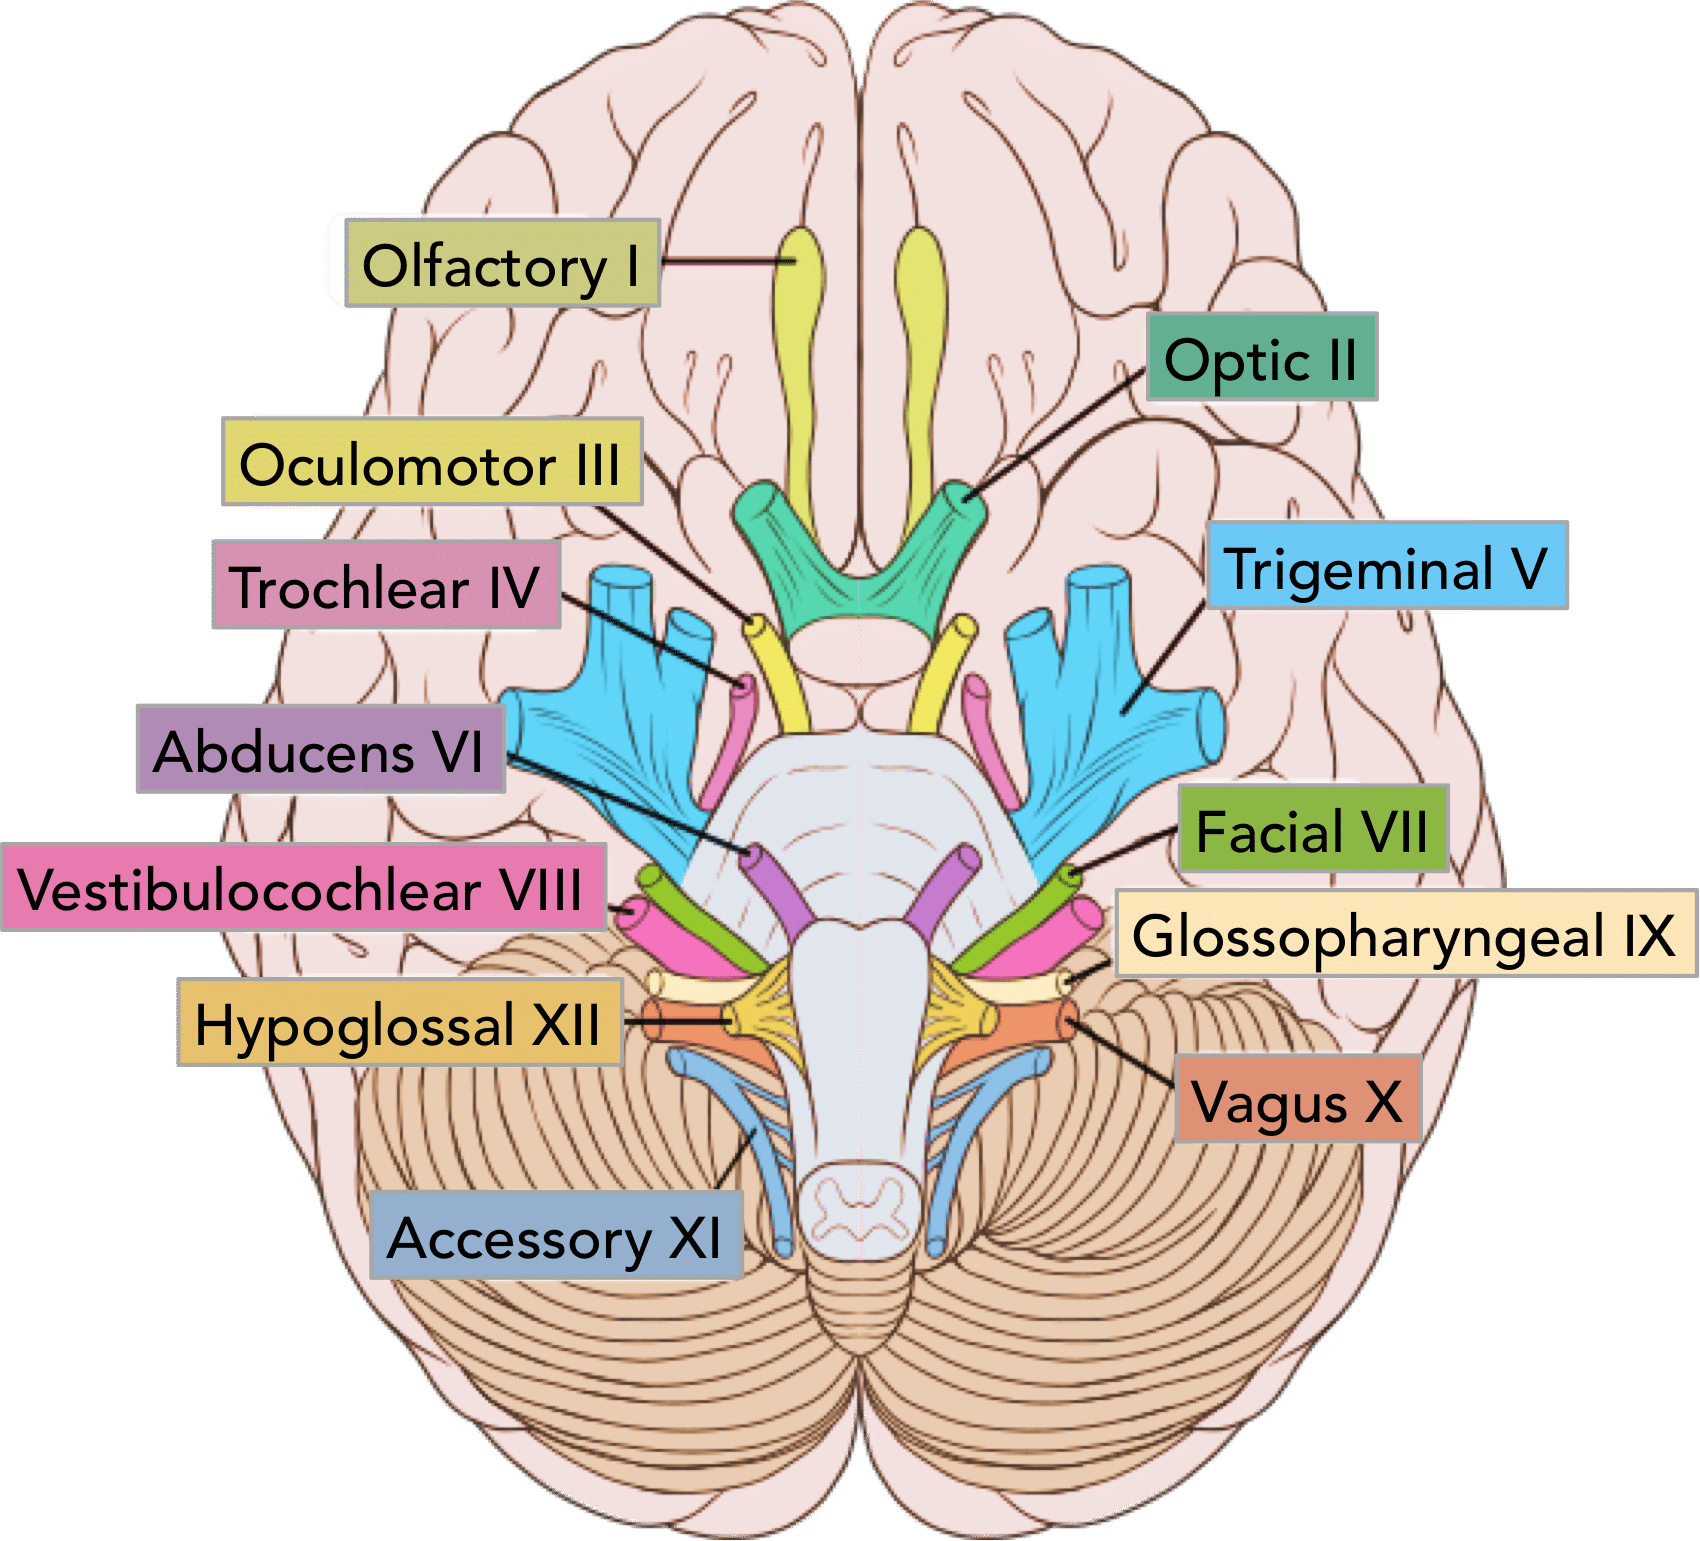

Cranial Nerves